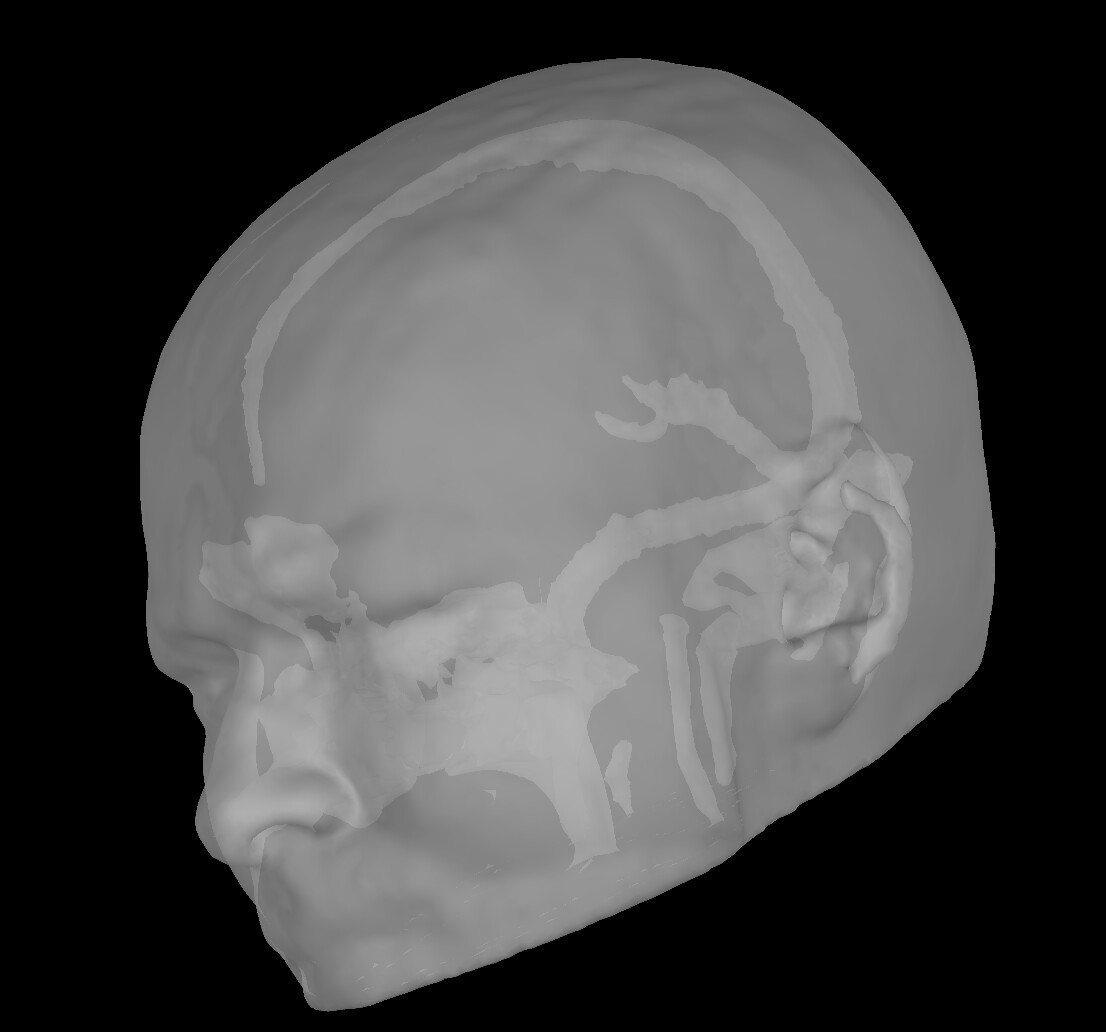

As a matter of fact, while the FEM model seems to do a good tissue characterisation, all the surfaces I have extracted within Brainstorm are wrong. For example, the scalp seems to have some skull embedded within

or, for example, the skull seems the CSF(?)